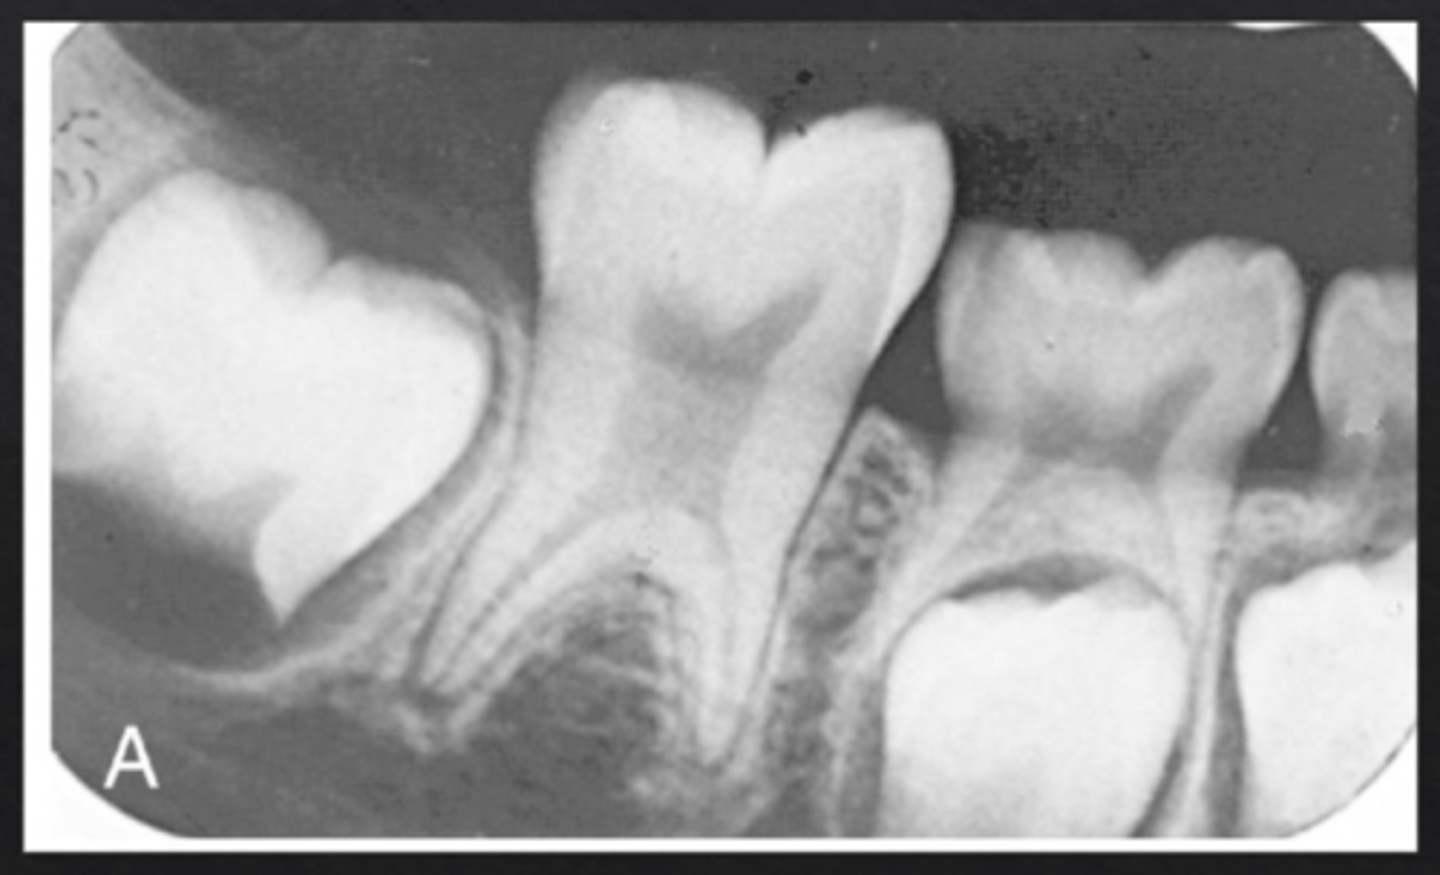

What is concrescence?

Fusion of the cementum of two adjacent teeth